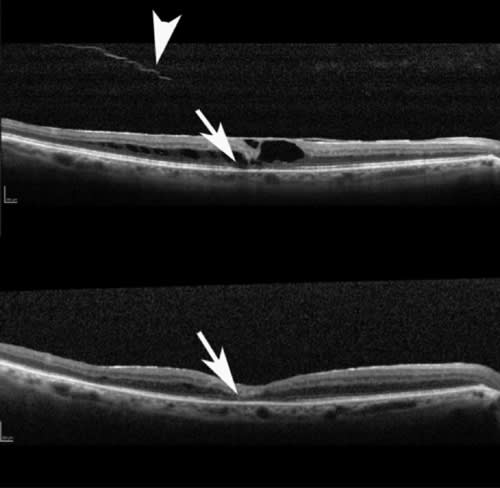

Figure 2. Horizontal raster SD-OCT scans in an eye with vitreomacular traction.

Top: scan through fovea showing a lamellar hole and posterior hyaloid with attachment nasally causing retinal traction.

Middle: Scan below the fovea showing attachment of posterior hyaloid with increased retinal thickness.

Bottom: Scan below the fovea showing posterior hyaloid with retinal traction causing plication (areas of loose adhesions between posterior hyaloid and retina). Raster scans give important information about the extent of traction and are helpful in surgical planning.

Figure 3. Vertical raster SD-OCT scans of the same eye as in Figure 2 showing posterior hyaloid causing vitreomacular traction with plication. Area of haze above and below the posterior hyaloid is artifact and does not represent vitreous gel.